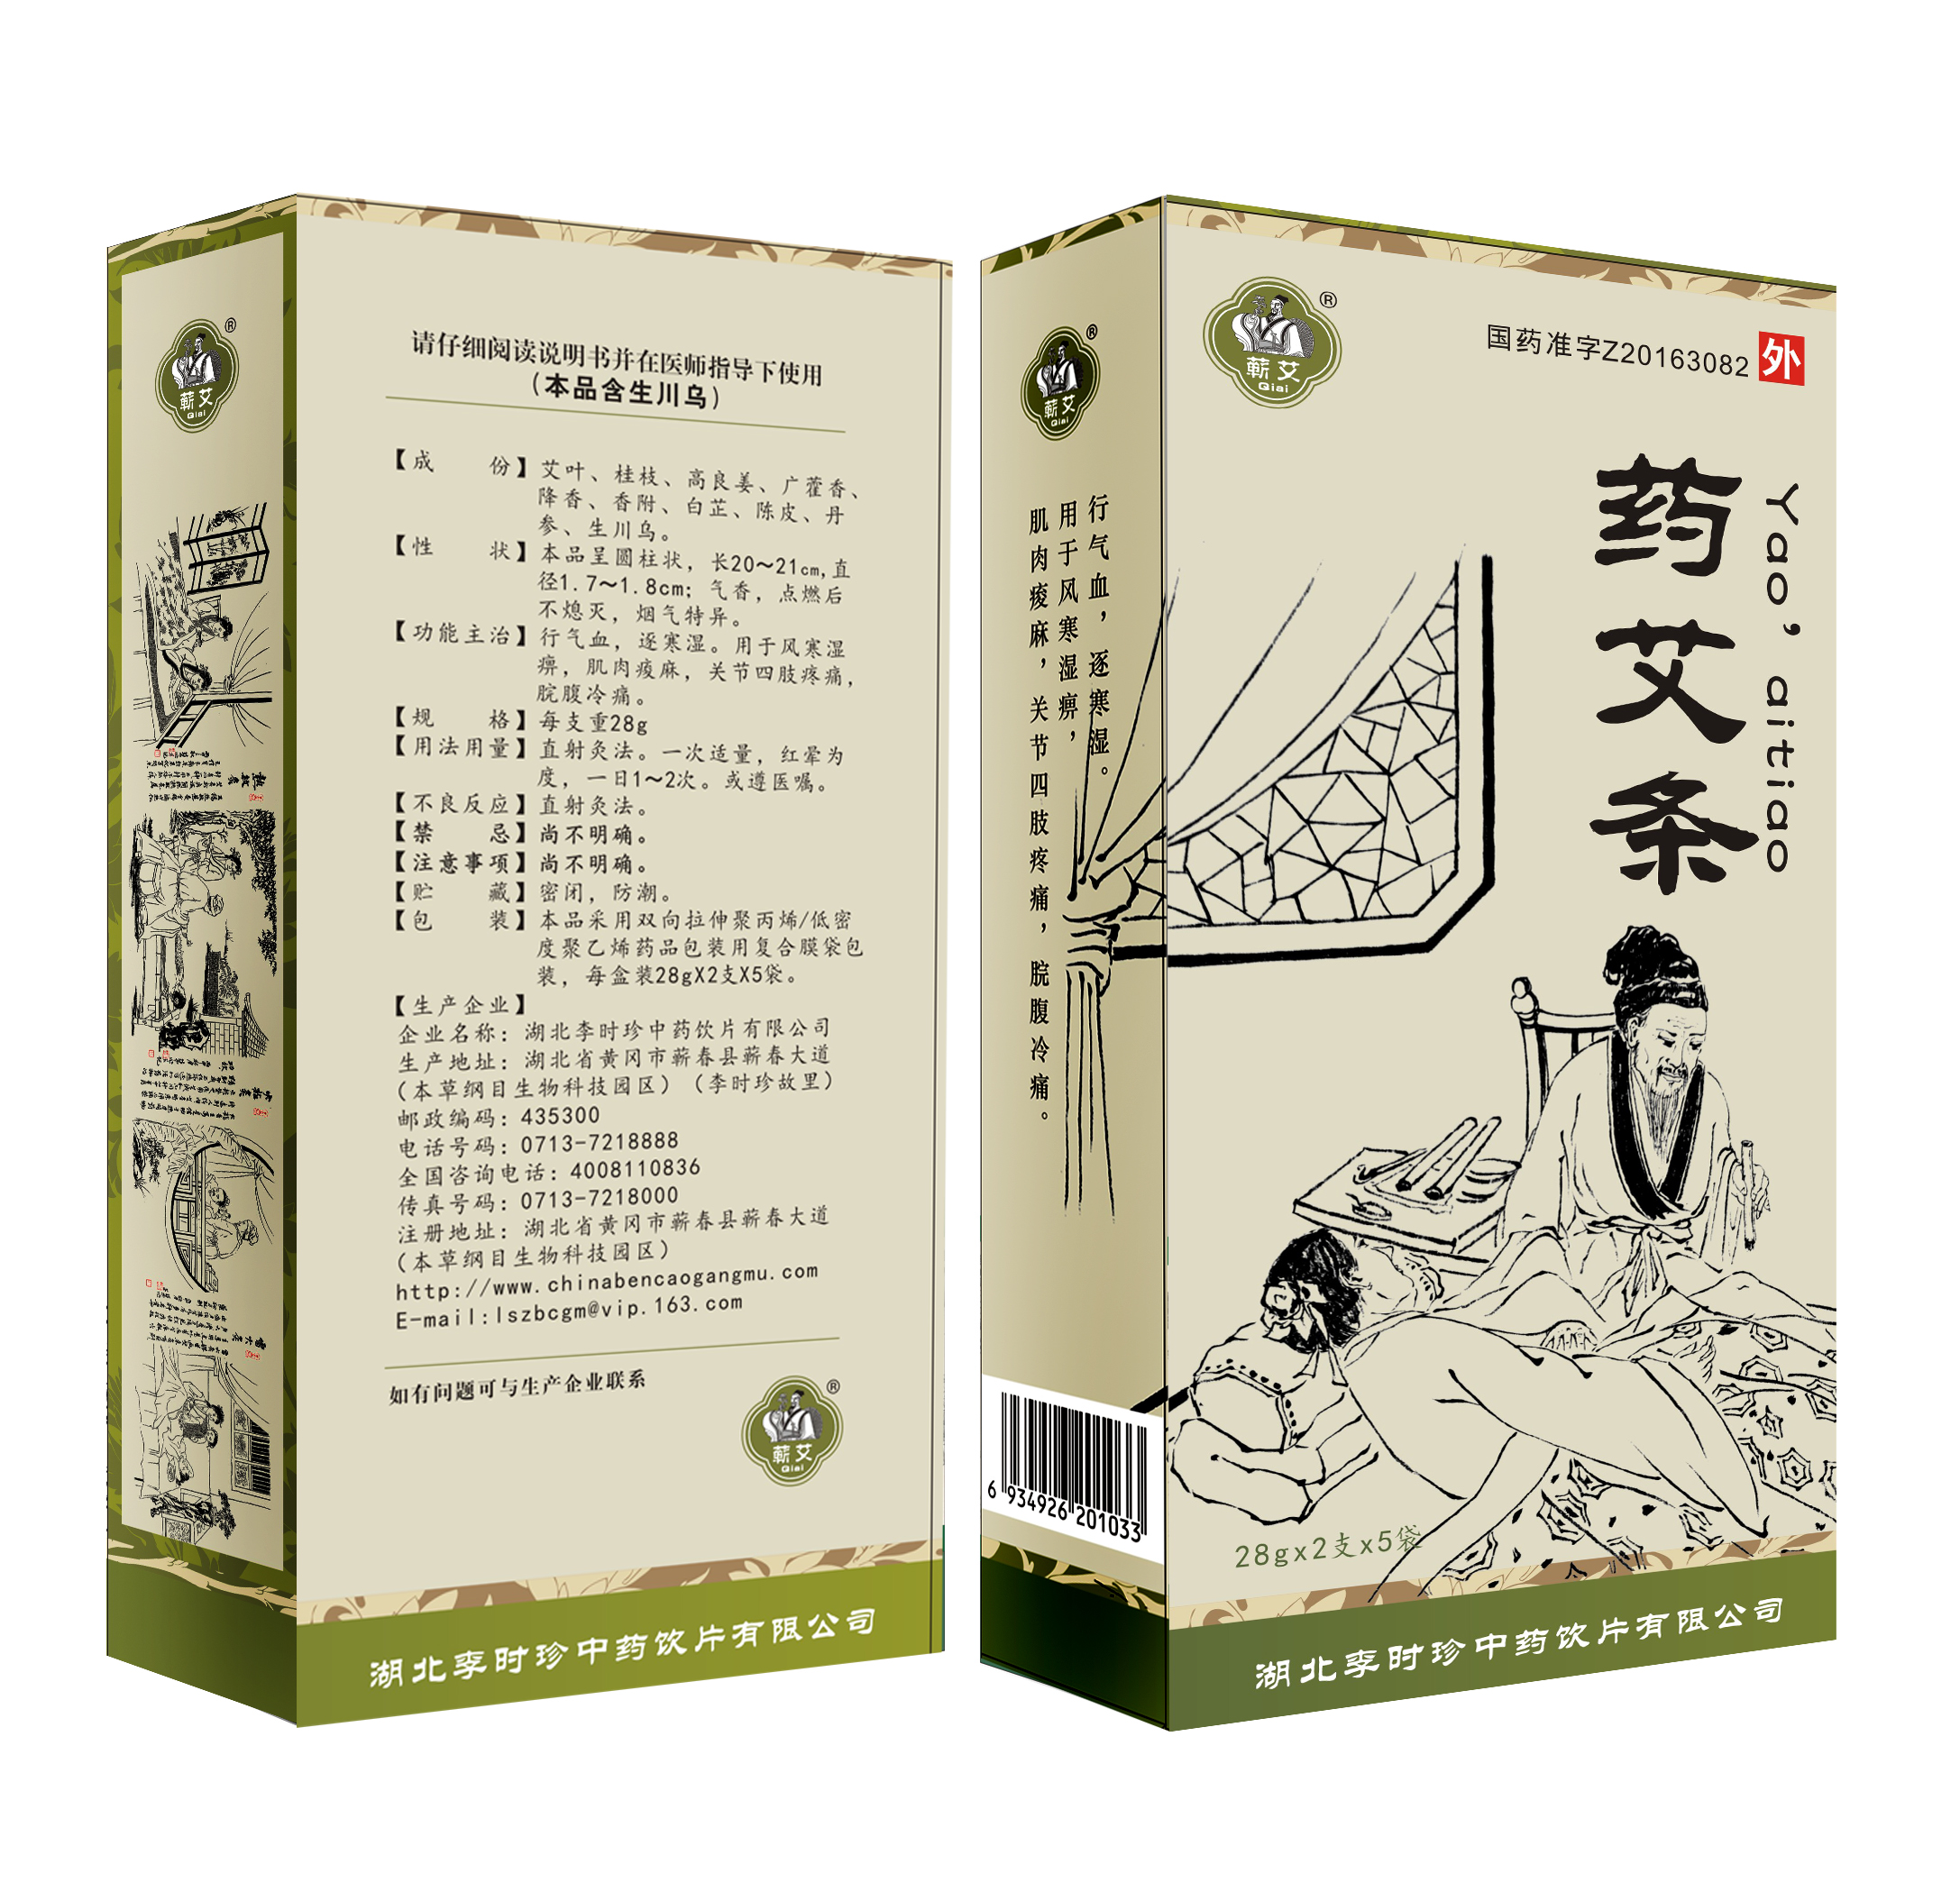

“传时珍医药伟业,谱本草科学新篇”,医药集团致力为广大用户提供一系列高质量的产品,涵盖了中成药、中药饮片、中药配方颗粒、保健酒、蕲艾系列大健康产品生产以及子公司厦门美商医药的化药。我们的产品结合了传统中医药炮制与现代科学技术,为用户提供健康、安全和有效的医药保健解决方案。 医药集团主要生产中成药品种近100个,其中40余个基药品种可纳入医保目录。此外,集团还生产中药配方颗粒品种350余个,中药饮片品种700余个,以及蕲艾制品100余个。这些产品经过多次的GMP认证,保证其质量和安全性。